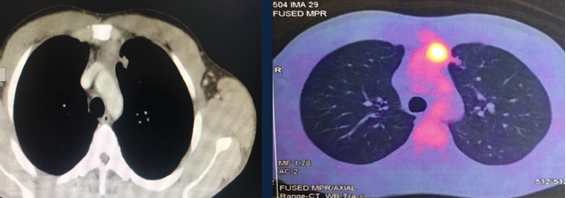

PET – CT: Persistence of a hypermetabolic residual mass (SUV max 7.8) of 48 x 32 x 70 mm is observed in the anterior mediastinum.

A 32-year-old man was referred with a diagnosis of an extragonadal germ cell tumor in the anterior mediastinum. Initially, he was treated with four cycles of chemotherapy (bleomycin, etoposide phosphate, and cisplatin), after which a PET-CT demonstrated a persistent hypermetabolic mass (SUV max 7.8) in the anterior mediastinum measuring 48 x 32 x 70 mm, without other metabolic abnormalities. Alpha-fetoprotein (AFP), LDH, and human chorionic gonadotrophin serum levels were normal. A radical surgical resection was recommended due to persistent residual disease. It was performed via a sternotomy with mediastinal tumor resection, pulmonary segmentectomy, and left diaphragm plication, due to resection of the involved phrenic nerve. The pathology results showed an embryonal carcinoma, 90 x 70 x 40 mm, with lung parenchyma involvement and 24% necrosis. There was no lymphovascular invasion, 1 of 4 lymph nodes had metastasis, and the margins were negative. Markers CD117 and CD30 were positive, AFP was negative. The patient recovered well. He was discussed in a tumor conference and was recommended to undergo adjuvant chemotherapy followed by bone marrow transplant.